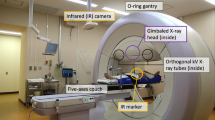

Different strategies have been proposed to account for respiratory motion [20, 21]: active breath-hold techniques [22], abdominal compression techniques [23], gating during end-expiration [24], motion-encompassing methods (Internal Target Volume (ITV) concept) [25], and respiration-synchronized techniques (tumor tracking approach) [25]. Tumor tracking is an advanced motion management strategy, which adjusts dynamically the treatment beam [26–28] or the patient position [29, 30] to the tumor motion.

Currently, most clinics use the ITV concept, which accounts for the whole tumor motion resulting in broad safety margins. However, among the aforementioned motion management methods, the tumor tracking is recognized as an advanced method of managing respiratory motion reducing the size of the planning target volume (PTV). This might lead to improved targeting and better tumor control while minimizes the radiation-induced toxicity to normal tissue. Real-time tracking of the pancreatic target has been mainly performed by a robotic arm-mounted linear accelerator [31] which utilizes prediction and correlation models [32–34] in order to relate the external breathing signals to 3D tumor motion (Cyberknife Synchrony, Saunnyvale, CA).

The aim of this study was to investigate the possible dosimetric advantages of using a tumor tracking approach compared with the ITV concept to account for respiratory-induced pancreatic tumor motion during gantry-based SBRT. For a better estimation of the dose in the moving tumor, we implemented 4D dose calculation of SBRT treatments with the ITV [25, 35] and the tumor tracking approach [25, 36, 37]. This allows to include respiratory motion effects into the evaluation of both motion managements strategies, which has not been done before so far for pancreatic tumors. Additionally, the differences between the 3D and 4D dose calculations were evaluated for both motion management strategies.